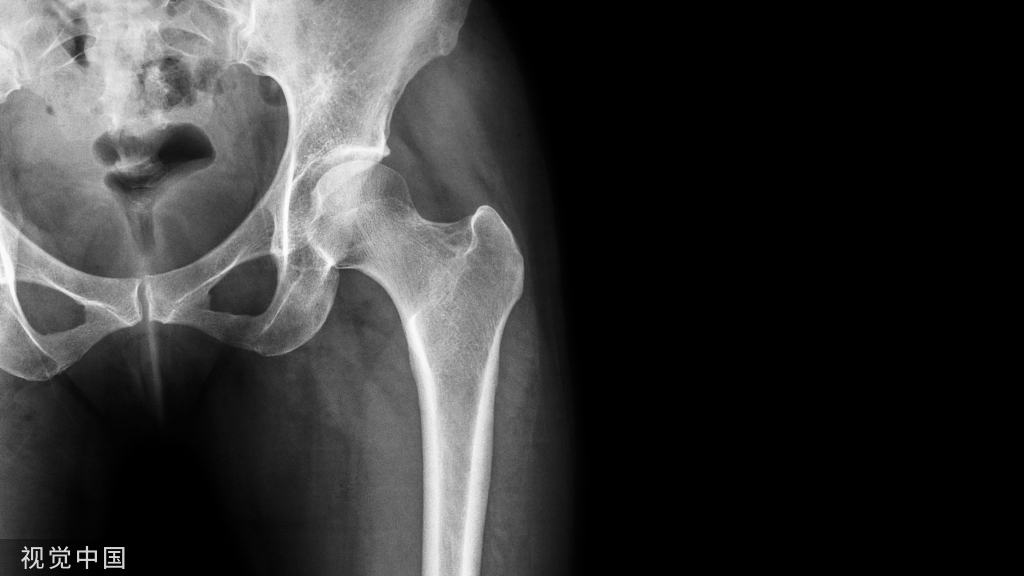

说到复位的细节,就要了解肱骨远端的解剖

1.解剖中比较重要的就是柱的概念,分为外侧柱和内侧柱,一个重要的滑车结构包含了300度的关节面,在外侧有一个肱骨小头的结构,然后一个冠突窝的结构

2.其中有几个重要的角度,4-8度的轻微外翻角,30度前方的前倾角

肱骨的内外侧柱和滑车构成了一个三角形稳定结构,手术复位的时候一定要完成稳定三角结构的恢复。